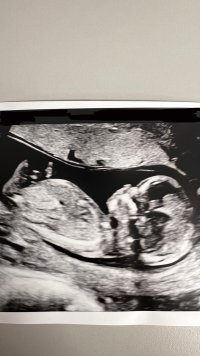

Her er vårt litt nurk fra i dag. Flyttet fire dager frem. Alt så fint ut. Både jordmor og jeg føler oss ganske sikre på at det er en gutt. Sprella og koste seg. Var veldig betryggende etter mange uker uten andre symptomer enn voksende mage. Kom ei pittelita tåre i øyekroken.

13+1 i dag da.